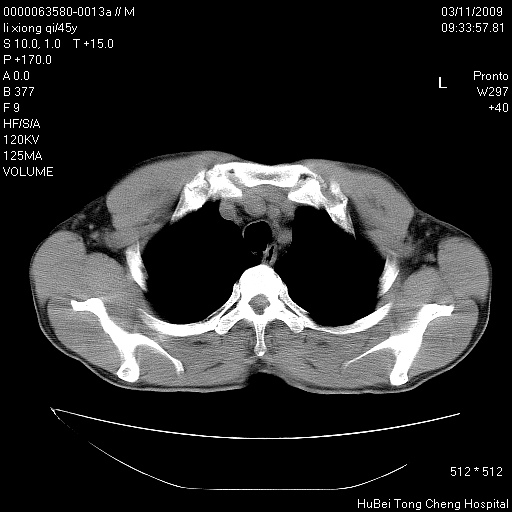

患者 男,45岁。胸痛,咳嗽伴痰中带血1月余。

临床诊断:肺结核?

胸部ct轴位平扫(层厚10mm,螺距1.5,重建间隔10mm),图像如下: